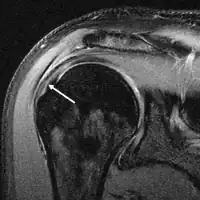

MRI

Magnetic resonance imaging (MRI) and ultrasound[42] are comparable in efficacy and helpful in diagnosis although both have a false positive rate of 15 - 20%.[43] MRI can reliably detect most full-thickness tears although very small pinpoint tears may be missed. In such situations, an MRI combined with an injection of contrast material, an MR-arthrogram, may help to confirm the diagnosis. It should be realized that a normal MRI cannot fully rule out a small tear (a false negative) while partial-thickness tears are not as reliably detected.[44] While MRI is sensitive in identifying tendon degeneration (tendinopathy), it may not reliably distinguish between a degenerative tendon and a partially torn tendon. Again, magnetic resonance arthrography can improve the differentiation.[44] An overall sensitivity of 91% (9% false negative rate) has been reported indicating that magnetic resonance arthrography is reliable in the detection of partial-thickness rotator cuff tears.[44] However, its routine use is not advised, since it involves entering the joint with a needle with potential risk of infection. Consequently, the test is reserved for cases in which the diagnosis remains unclear.